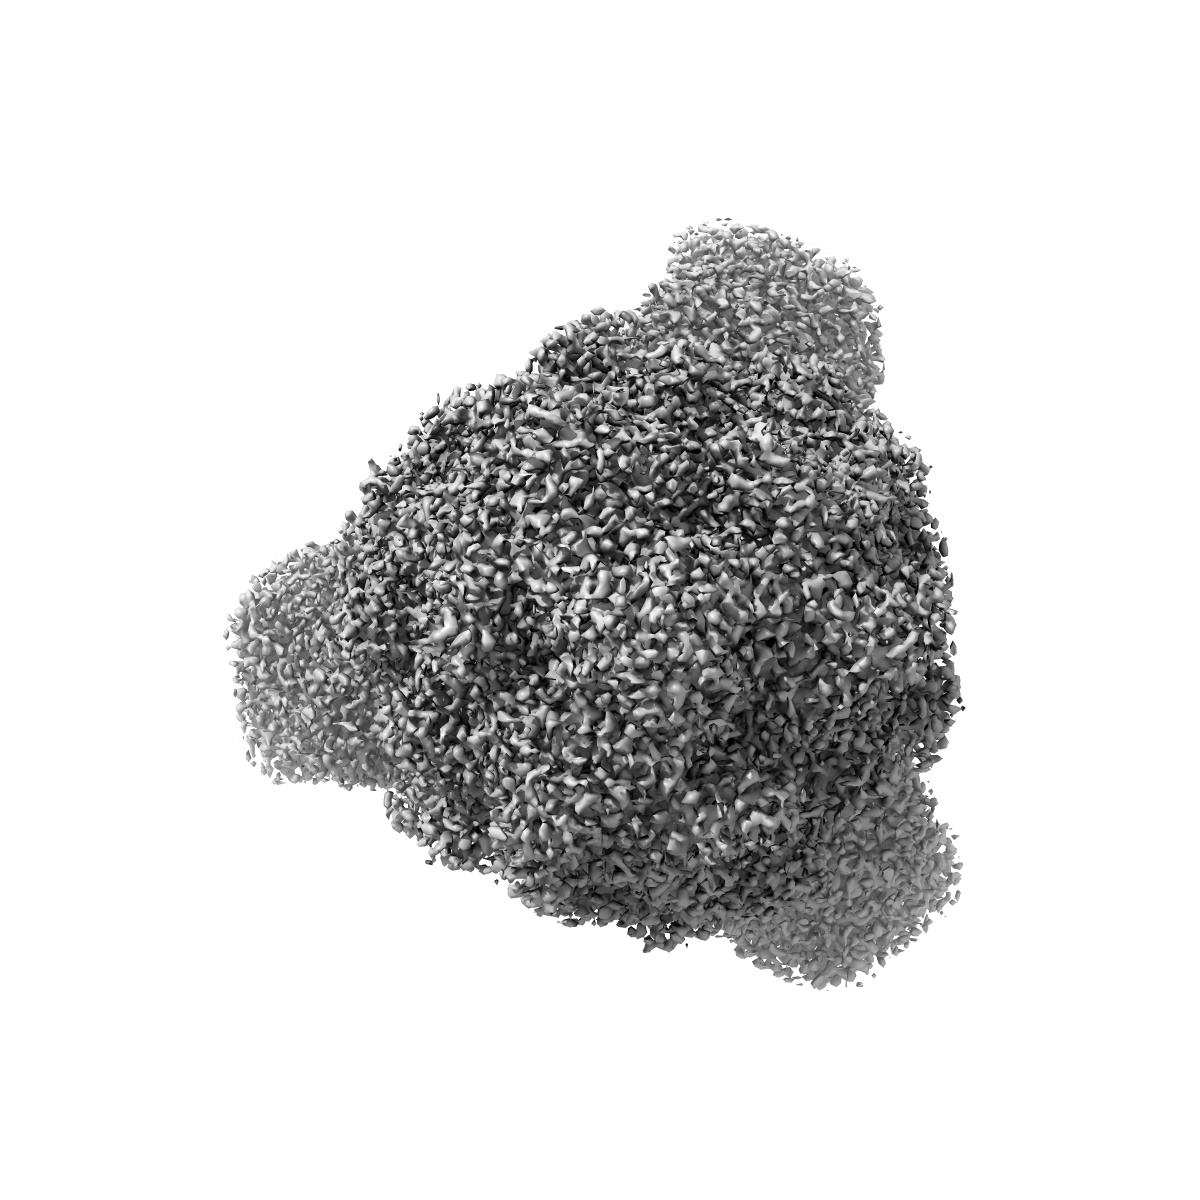

EMD-12818

SARS CoV-2 Spike protein, Bristol UK Deletion variant, Closed conformation, C3 symmetry

Single-particle2.8 Å

Sample: SARS CoV-2 Spike protein, Bristol UK Deletion variant, Closed conformation, C3 symmetry